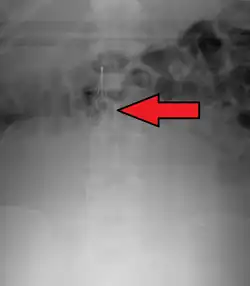

Placement

IVC filters are placed endovascularly, meaning that they are inserted via the blood vessels. Historically, IVC filters were placed surgically, but with modern filters that can be compressed into much thinner catheters, access to the venous system can be obtained via the femoral vein (the large vein in the groin), the internal jugular vein (the large vein in the neck) or the arm veins with one design. Choice of route depends mainly on the number and location of any blood clot within the venous system. To place the filter, a catheter is guided into the IVC using fluoroscopic guidance, then the filter is pushed through the catheter and deployed into the desired location, usually just below the junction of the IVC and the lowest renal vein.[44]

Review of prior cross-sectional imaging or a venogram of the IVC is performed before deploying the filter to assess for potential anatomic variations, thrombi within the IVC, or areas of stenoses, as well as to estimate the diameter of the IVC. Rarely, ultrasound-guided placement is preferred in the setting of contrast allergy, chronic kidney disease, and when patient immobility is desired. The size of the IVC may affect which filter is deployed, as some (such as the Birds Nest) are approved to accommodate larger cavae. There are situations where the filter is placed above the renal veins (e.g. pregnant patients or women of childbearing age, renal or gonadal vein thromboses, etc.). Also, if there is duplication of the IVC, the filter is placed above the confluence of the two IVCs [45] or a filter can be placed within each IVC.[46]